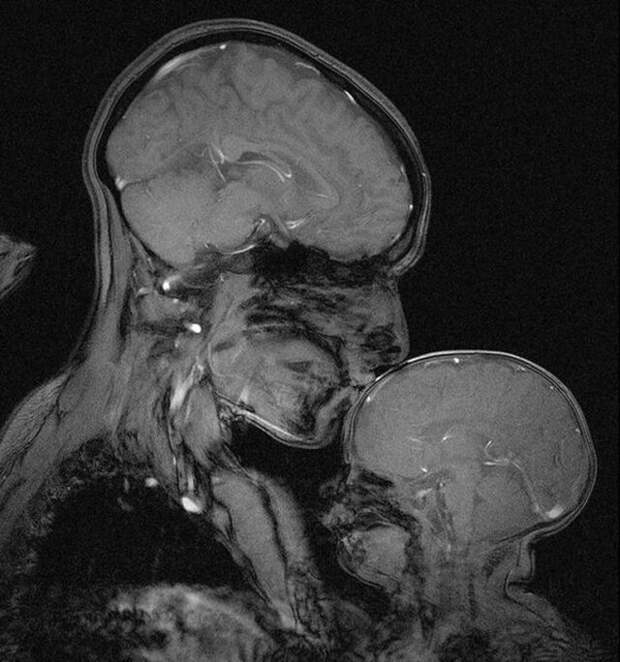

Зубы в семь лет и в тридцать  Мать и дитя в МРТ сканере

Мать и дитя в МРТ сканере